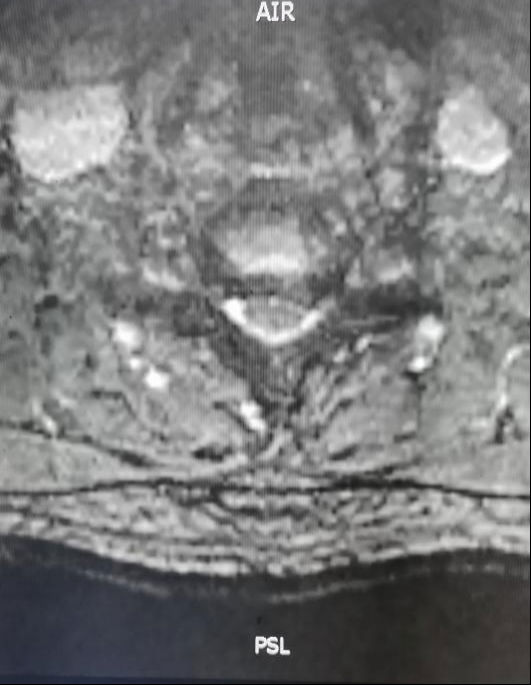

结合相关检查,患者被明确诊断为神经根型颈椎病,因颈6/7节段椎间盘向左后方突出,造成侧隐窝及椎间孔狭窄,压迫左侧颈7神经根,神经功能进行性下降。患者有明确手术指征,经过详细地医患沟通,患者最终选择用微创的手术方式进行治疗。